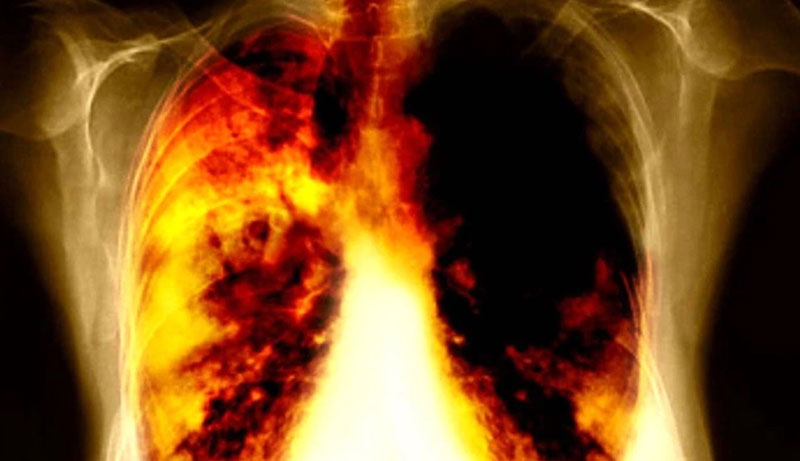

Những bất thường ở vùng đầu cảnh báo ung thư phổi? Nếu có 3 dấu hiệu này hãy đi khám càng sớm càng tốt!

Mặc dù ung thư phổi là một loại ung thư rất thầm lặng, ít triệu chứng và khó phát hiện khi đã phát triển, nhưng nếu bạn nhận thấy 3 dấu hiệu bất thường ở vùng đầu hãy đi khám sớm.

(Ảnh minh họa: Internet)